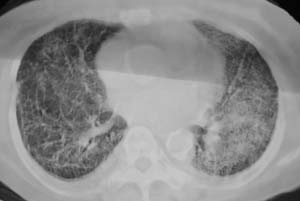

以下是引用liaizhi在2007-7-6 0:05:00的发言:[br]双肺纹理膜糊,沿纹理走行有班点状高密度影。考虑心衰并肺水肿。

以下是引用andymaomao在2007-7-5 22:23:00的发言:[br]双上肺明显,考虑心衰并肺水肿,双侧胸腔少量积液!另不除外肺泡蛋白沉着症及肺泡ca可能。[br]联想机制——心脏病(代偿期)--肺部淤血--后可能并感染致病情加重--抗炎治疗好转,但肺淤血严重,心功能失代偿--心衰而死亡!

以下是引用拾荒者在2007-7-6 13:06:00的发言:[br]支持:心衰,肺水肿及ards